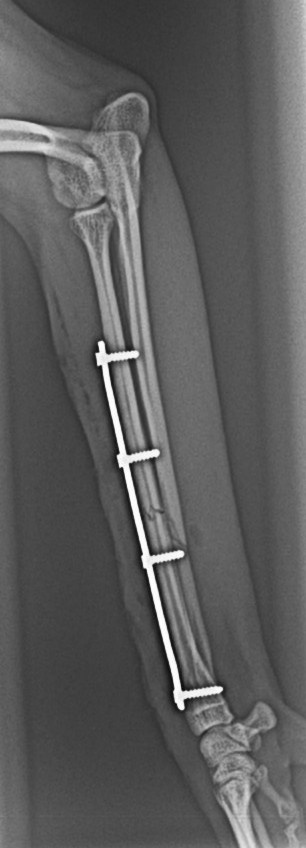

・骨折手術(プレート固定など)

・橈尺骨(前肢)骨折整復術 45万円前後